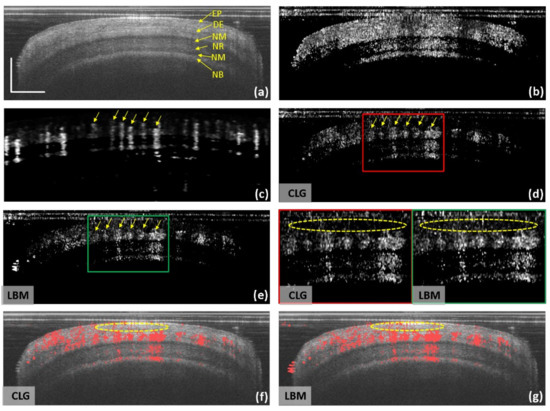

As the skin tissue around the nailfold region contains characteristic structures with rich blood perfusion, the little finger nailfold on the left hand of a healthy female volunteer was imaged with the endoscopic catheter and the conventional galvanometric scanner. In the endoscopic cross-sectional structure (Figure 4a), the epidermis (EP), dermis (DE), nail matrix (NM), nail root (NR), and nail beds (NB) layers were clearly differentiated. The blood vessels were supposed to be mainly distributed within the DE layer [34]. The endoscopic cross-sectional IDa-OCTA angiogram without distortion correction is shown in Figure 4b, where the dynamic flows in the DE layer were not distinguishable from the neighbor static tissue. For comparison, a galvanometric scanner was used to image a similar little finger nailfold region, and the conventional cross-sectional IDa-OCTA angiogram (Figure 4c) was obtained, where the blood vessels could be clearly identified from the background with a high contrast. After performing distortion correction on endoscopic structures, the corresponding CLG-corrected endoscopic IDa-OCTA (Figure 4d) and LBM-corrected endoscopic IDa-OCTA (Figure 4e) both enabled a relatively clear visualization of the blood perfusion within the high scattering skin tissue, and the endoscopic angiograms had a good correspondence with the conventional angiogram (see the yellow arrow in Figure 4c–e), demonstrating the reality of the dynamic flow obtained by the endoscopic proximal-end scanning catheter. Compared with the CLG-corrected angiogram, the LBM-corrected angiogram had a higher background noise and thus a lower image contrast, partly circled by yellow ellipses in the insets. In addition, the noisy background also impaired the vessel density evaluation. As shown in Figure 4f,g, the binarized vascular masks of CLG- and LBM-corrected angiograms (red) were overlayed on the structural image, and the CLG-corrected image showed less noisy points labeled by yellow ellipses, enabling a higher accuracy in vessel density evaluation.

Figure 4. IDa-OCTA imaging of the little finger nailfold of a healthy volunteer with the endoscopic clinical proximal-end scanning catheter and the conventional galvanometric scanner. (a) Endoscopic cross-sectional structure of the nailfold. (b) Endoscopic cross-sectional IDa-OCTA angiogram before correction. (c) Conventional cross-sectional IDa-OCTA angiogram obtained by imaging a similar nailfold position with a galvanometric scanner. Endoscopic cross-sectional IDa-OCTA angiogram after using CLG correction (d) and after using LBM correction (e). Left insets are enlarged views of the enclosed areas. Corresponding vessels are labeled by the yellow arrows. Overlay of the CLG-corrected endoscopic IDa-OCTA angiogram (red, (f)) and the LBM-corrected endoscopic IDa-OCTA angiogram (red, (g)) on the cross-sectional structure (gray). Corresponding residual noise is circled by yellow ellipses. EP: epidermis, DE: dermis, NM: nail matrix, NR: nail root, NB: nail bed. A kernel of 5 × 3 × 5 (z × x × t) was adopted in IDa-OCTA calculation. Scale bar = 0.5 mm.